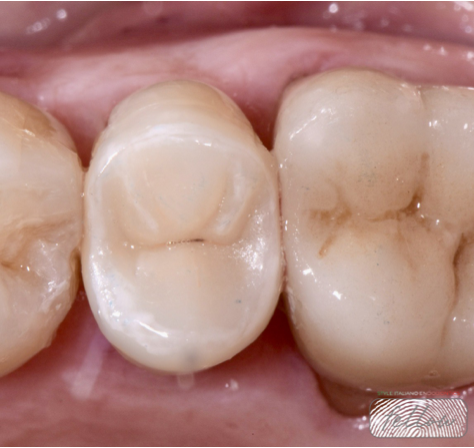

Fig. 7

Final cementation of the indirect overlay restoration was carried out.Indirect overlays generally show better fracture resistance and higher survival rates compared to large direct fillings on endodontically treated teeth.